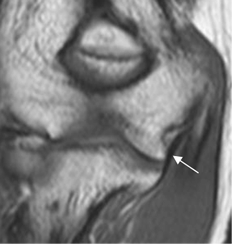

El seudodefecto troclear, tiene similares características y se aprecia hacia el fondo de la cavidad troclear del cúbito. (Fig 9).

Fig 9. Seudodefecto troclear.

A: Rx lateral y B: RM sagital en T1. Irregularidad en la cortical de la cavidad coronoides.

C: RM sagital en STIR. Estudio normal, descartando lesiones óseas.